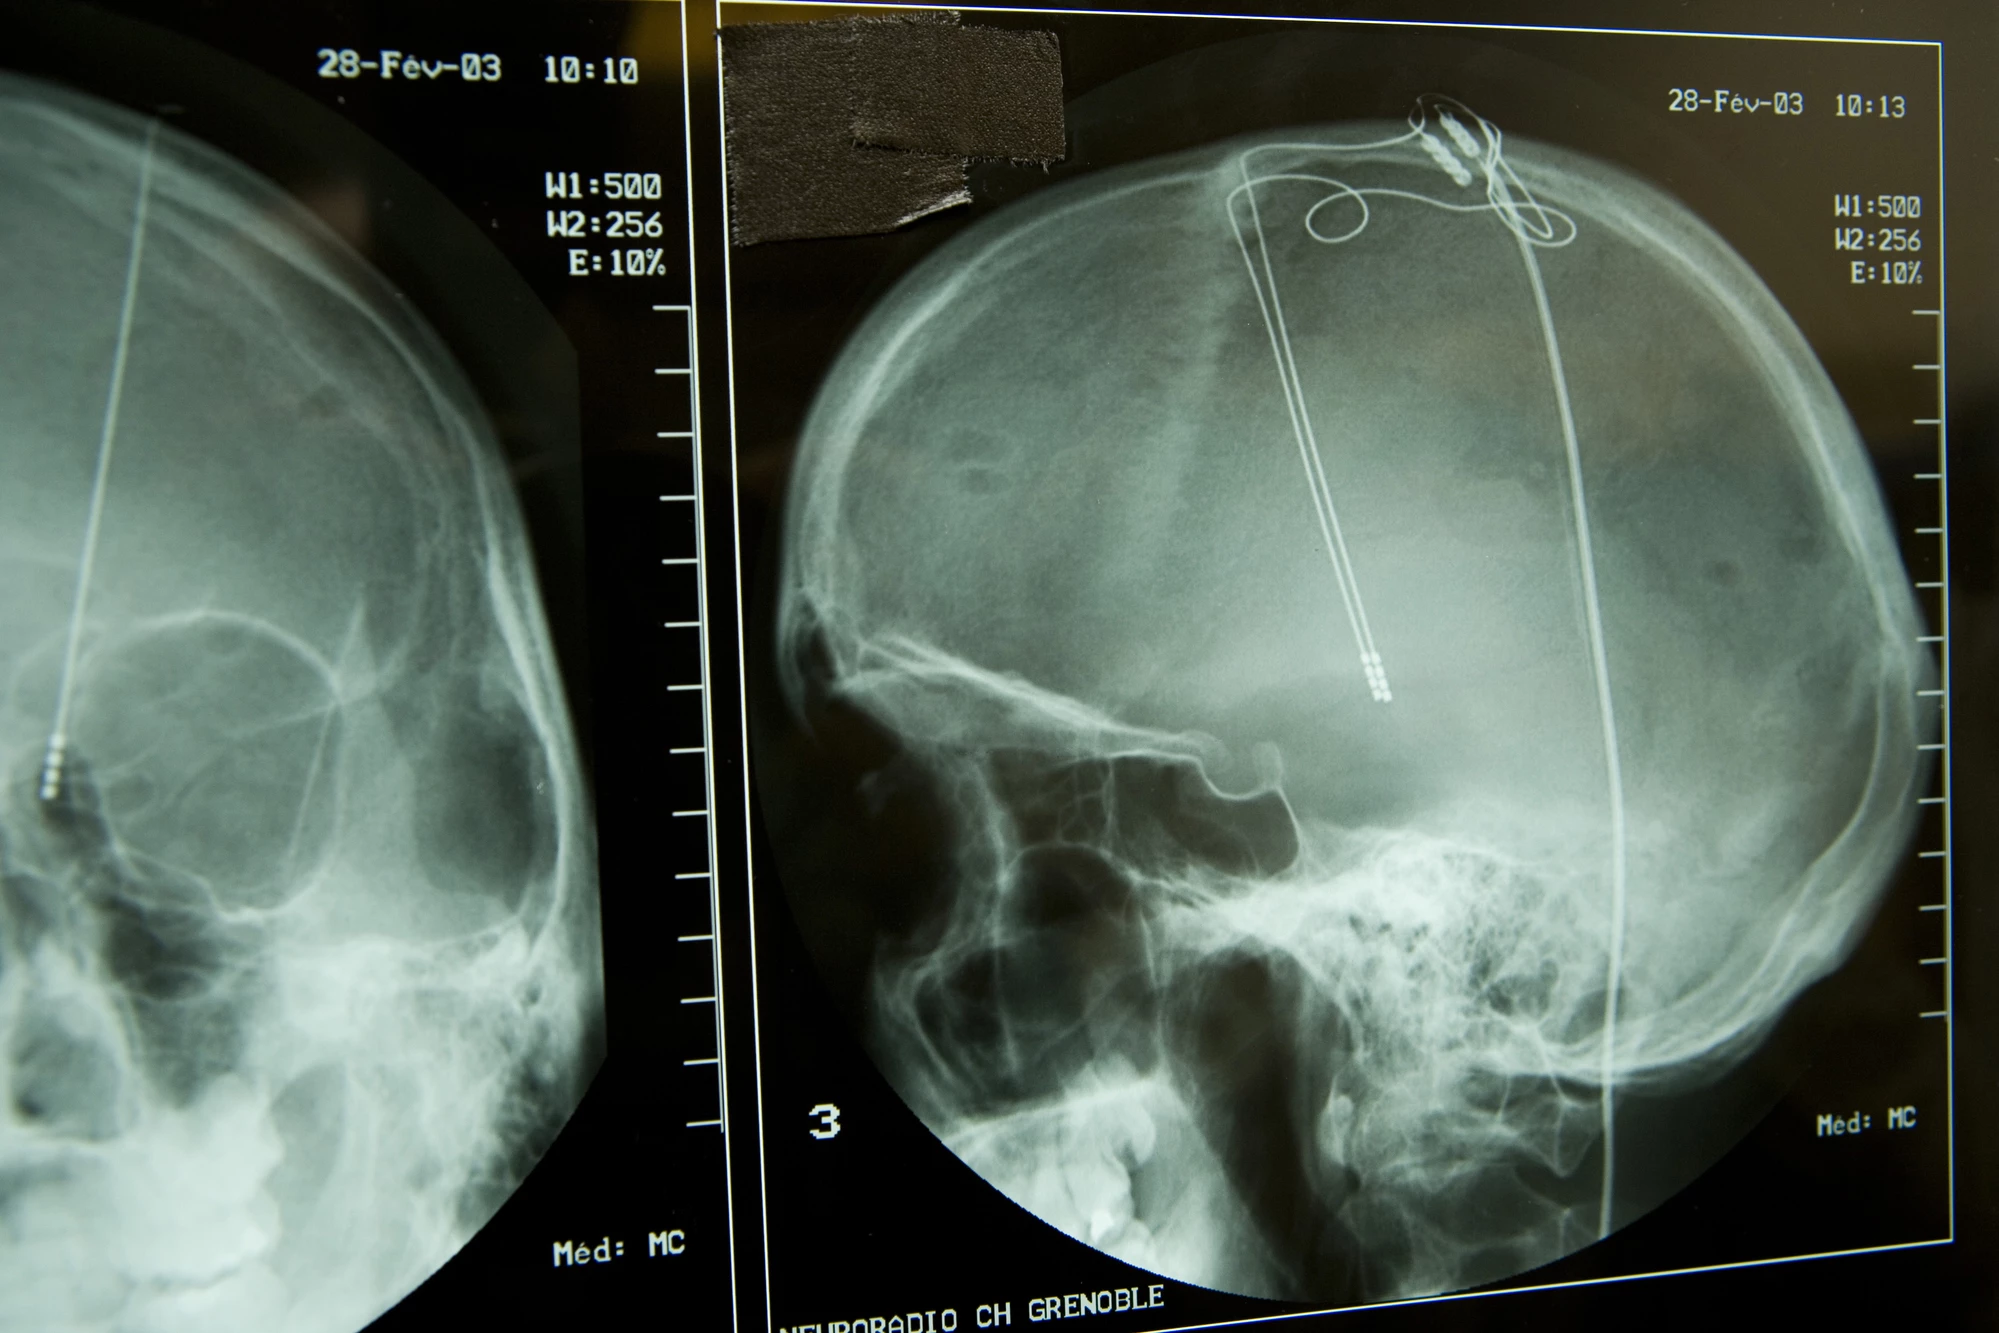

Deep brain stimulation (DBS) has been used to treat symptoms in Parkinson’s disease sufferers for several decades. The treatment involves several tiny wires being implanted into a patient’s brain, primarily targeting areas connecting to the ventral thalamus. Applying sporadic electrical currents directly to certain parts of the brain has been found to consistently reduce symptoms including tremors, muscle stiffness and slowed movement.

Seven Parkinson’s patients, with implanted DBS electrodes, were administered PET scans before and after electrical stimulation was applied. Symptoms were evaluated following the application of DBS to verify the process had worked, and analyzing the PET scans did indeed reveal VMAT2 levels dropped following the electrical stimulation.